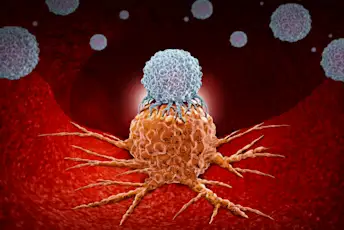

了解你的T细胞

你可能认不出这些增强的抗癌白细胞。这是你的re-introduction。